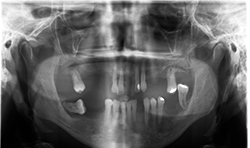

Case 2:66-year-old woman with edentulous maxillae

Two-dimensional imaging can’t evaluate the volume of the alveolar process accurately, especially in the buccolingual direction (Fig. 3)

CBCT imaging shows the volume of the alveolar process in any direction for implant treatment planning. (Figs. 4A, 4B) CBCT software allows one to measure the height and width of the alveolar ridge (Fig. 4C). This patient doesn’t have adequate bone volume for implant placement in the posterior left maxilla (Fig. 4D). Due to the severe alveolar ridge resorption, gaining adequate bone volume was recommended.